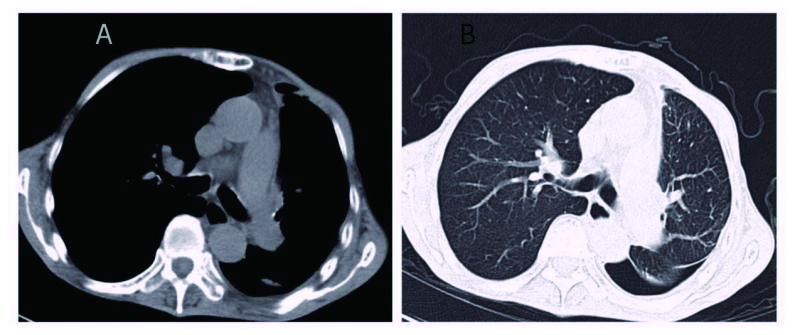

1 资料与方法患者男,70岁,农民,入院前3 d受凉后出现咳嗽,为阵发性干咳、无痰,伴胸闷、气喘,平卧及活动时加重,发热,体温最高37.7 ℃,热型未监测,无畏冷、寒战;当地医院胸部X线平片示左侧胸腔积液、左侧肺炎,予以“头孢噻肟”抗感染治疗无效,于2015年9月29日转来厦门大学附属第一医院。既往慢性支气管炎病史20余年,吸烟史50年×40支/d。入院时查体:T 37.6 ℃,P 106次/min,R 26次/min,BP 118/72 mmHg,SPO2 91%,神志清楚,反应迟钝,有时答非所问,呼吸较急促,气管轻度右偏;左侧胸部呼吸运动减弱,语颤消失,叩诊呈浊音,呼吸音减弱,右肺散在哮鸣音;心界不清,心率106次/min,节律规整,各瓣膜区未闻及杂音。入院后观察患者热型为不规则低热,查血尿粪常规、肝肾功能、肿瘤标志物等正常,降钙素原0.826 ng/mL,结核抗体及结核菌素实验阴性。血气分析:氧分压6.63 kPa,二氧化碳分压正常,无酸碱失衡表现。胸部CT示,双肺多发感染,左侧大量胸腔积液;右肺局限性肺大泡,肺气肿(图 1)。入院后给予莫西沙星抗感染,胸腔穿刺引流出大量淡红色稍混浊胸水,无臭味,每日引流量300~600 mL;胸水常规:李凡他试验阳性,蛋白48.6 g/L,有核细胞数1 520×106/L,比重1.021。患者仍有反复低热,热峰及持续时间稍改善。入院后10 d胸水培养结果回报为星型奴卡菌感染(图 3、4),抗生素更换为TMP-SMX 0.96 g/12 h联合红霉素0.25 g/8 h治疗,体温逐渐下降至正常,咳嗽、气喘症状缓解,胸水引流量逐渐减少至消失,PCT和血气分析结果恢复正常,胸部CT:左侧少量胸腔积液,伴积气(图 2)。于2015年10月25日出院,继续口服TMP-SMX片及红霉素片治疗,定期随诊。患者感觉恢复良好在出院后1个月左右自行停药,3个月后因右侧肢体无力再诊我院,颅脑MRI提示:大面积小脑梗死,脑疝并幕上脑积水(图 5),再诊时未再复查胸部CT,2 d后因呼吸循环衰竭死亡,家属未同意尸检。

| 图 1 左肺大量胸腔积液,左肺压缩近不显影(A:纵隔窗; B:肺窗) |